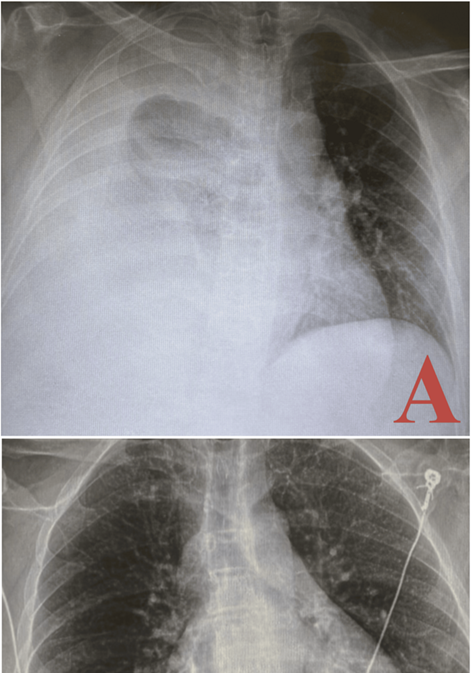

A

post-thoracentesis chest x-ray showed re-expansion of the right lung with

stable bibasilar opacities and minimal blunting of the right costophrenic

angle. Notably, there was a small right apical pneumothorax (figure 2).

Figure 2:

chest x-rays pre- and post-thoracentesis illustrating resolution of pleural

effusion: the pre-thoracentesis chest x-ray (a) shows a large right pleural

effusion with associated near-complete collapse of the right lung and leftward

mediastinal shift. The post-thoracentesis chest x-ray (b) demonstrates the

re-expansion of the right lung, with resolution of the effusion and minimal

residual blunting of the right costophrenic angle. A small right apical

pneumothorax is also observed.